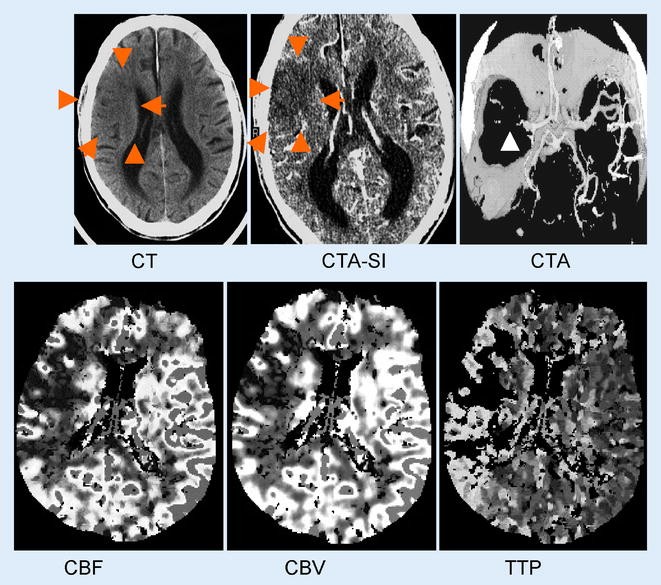

Die systemische lysetherapie ist gut untersucht und stellt international den akzeptierten standard der akutbehandlung dar. Gemäß den leitlinien der deutschen gesellschaft für neurologie ist die anwendung eines schnittbildgebenden verfahrens in der akutphase eines ischämischen schlaganfalls vor einleitung einer lysetherapie obligat. Die empirische 1 3 6 12 tage regel hilft jedoch zumeist weiter hat man bestimmte faktoren im blick. Der schlaganfall oder apoplexie ist eine erkrankung die durch eine minderung des blutflusses zum gehirn verursacht wird.

Einen schlaganfall muss für die anschließende therapie herausgefunden werden ob es sich um ein ischämisches oder um ein hämorrhagisches ereignis handelt. Ischämischer schlaganfall ii welearn inwitten. Diese unterscheidung ist am besten mit einem cct möglich. Die skala liefert einblicke in die lokalisation der gefäßläsion korreliert mit dem outcome ischämischer schlaganfälle und identifiziert kandidaten die für eine thrombolytische therapie in frage kommen.

Ct Perfusion Erhoht Therapiechancen Von Diagnoseverzogerten Patienten

Akuter Ischamischer Schlaganfall Moderne Techniken Verkurzen Die